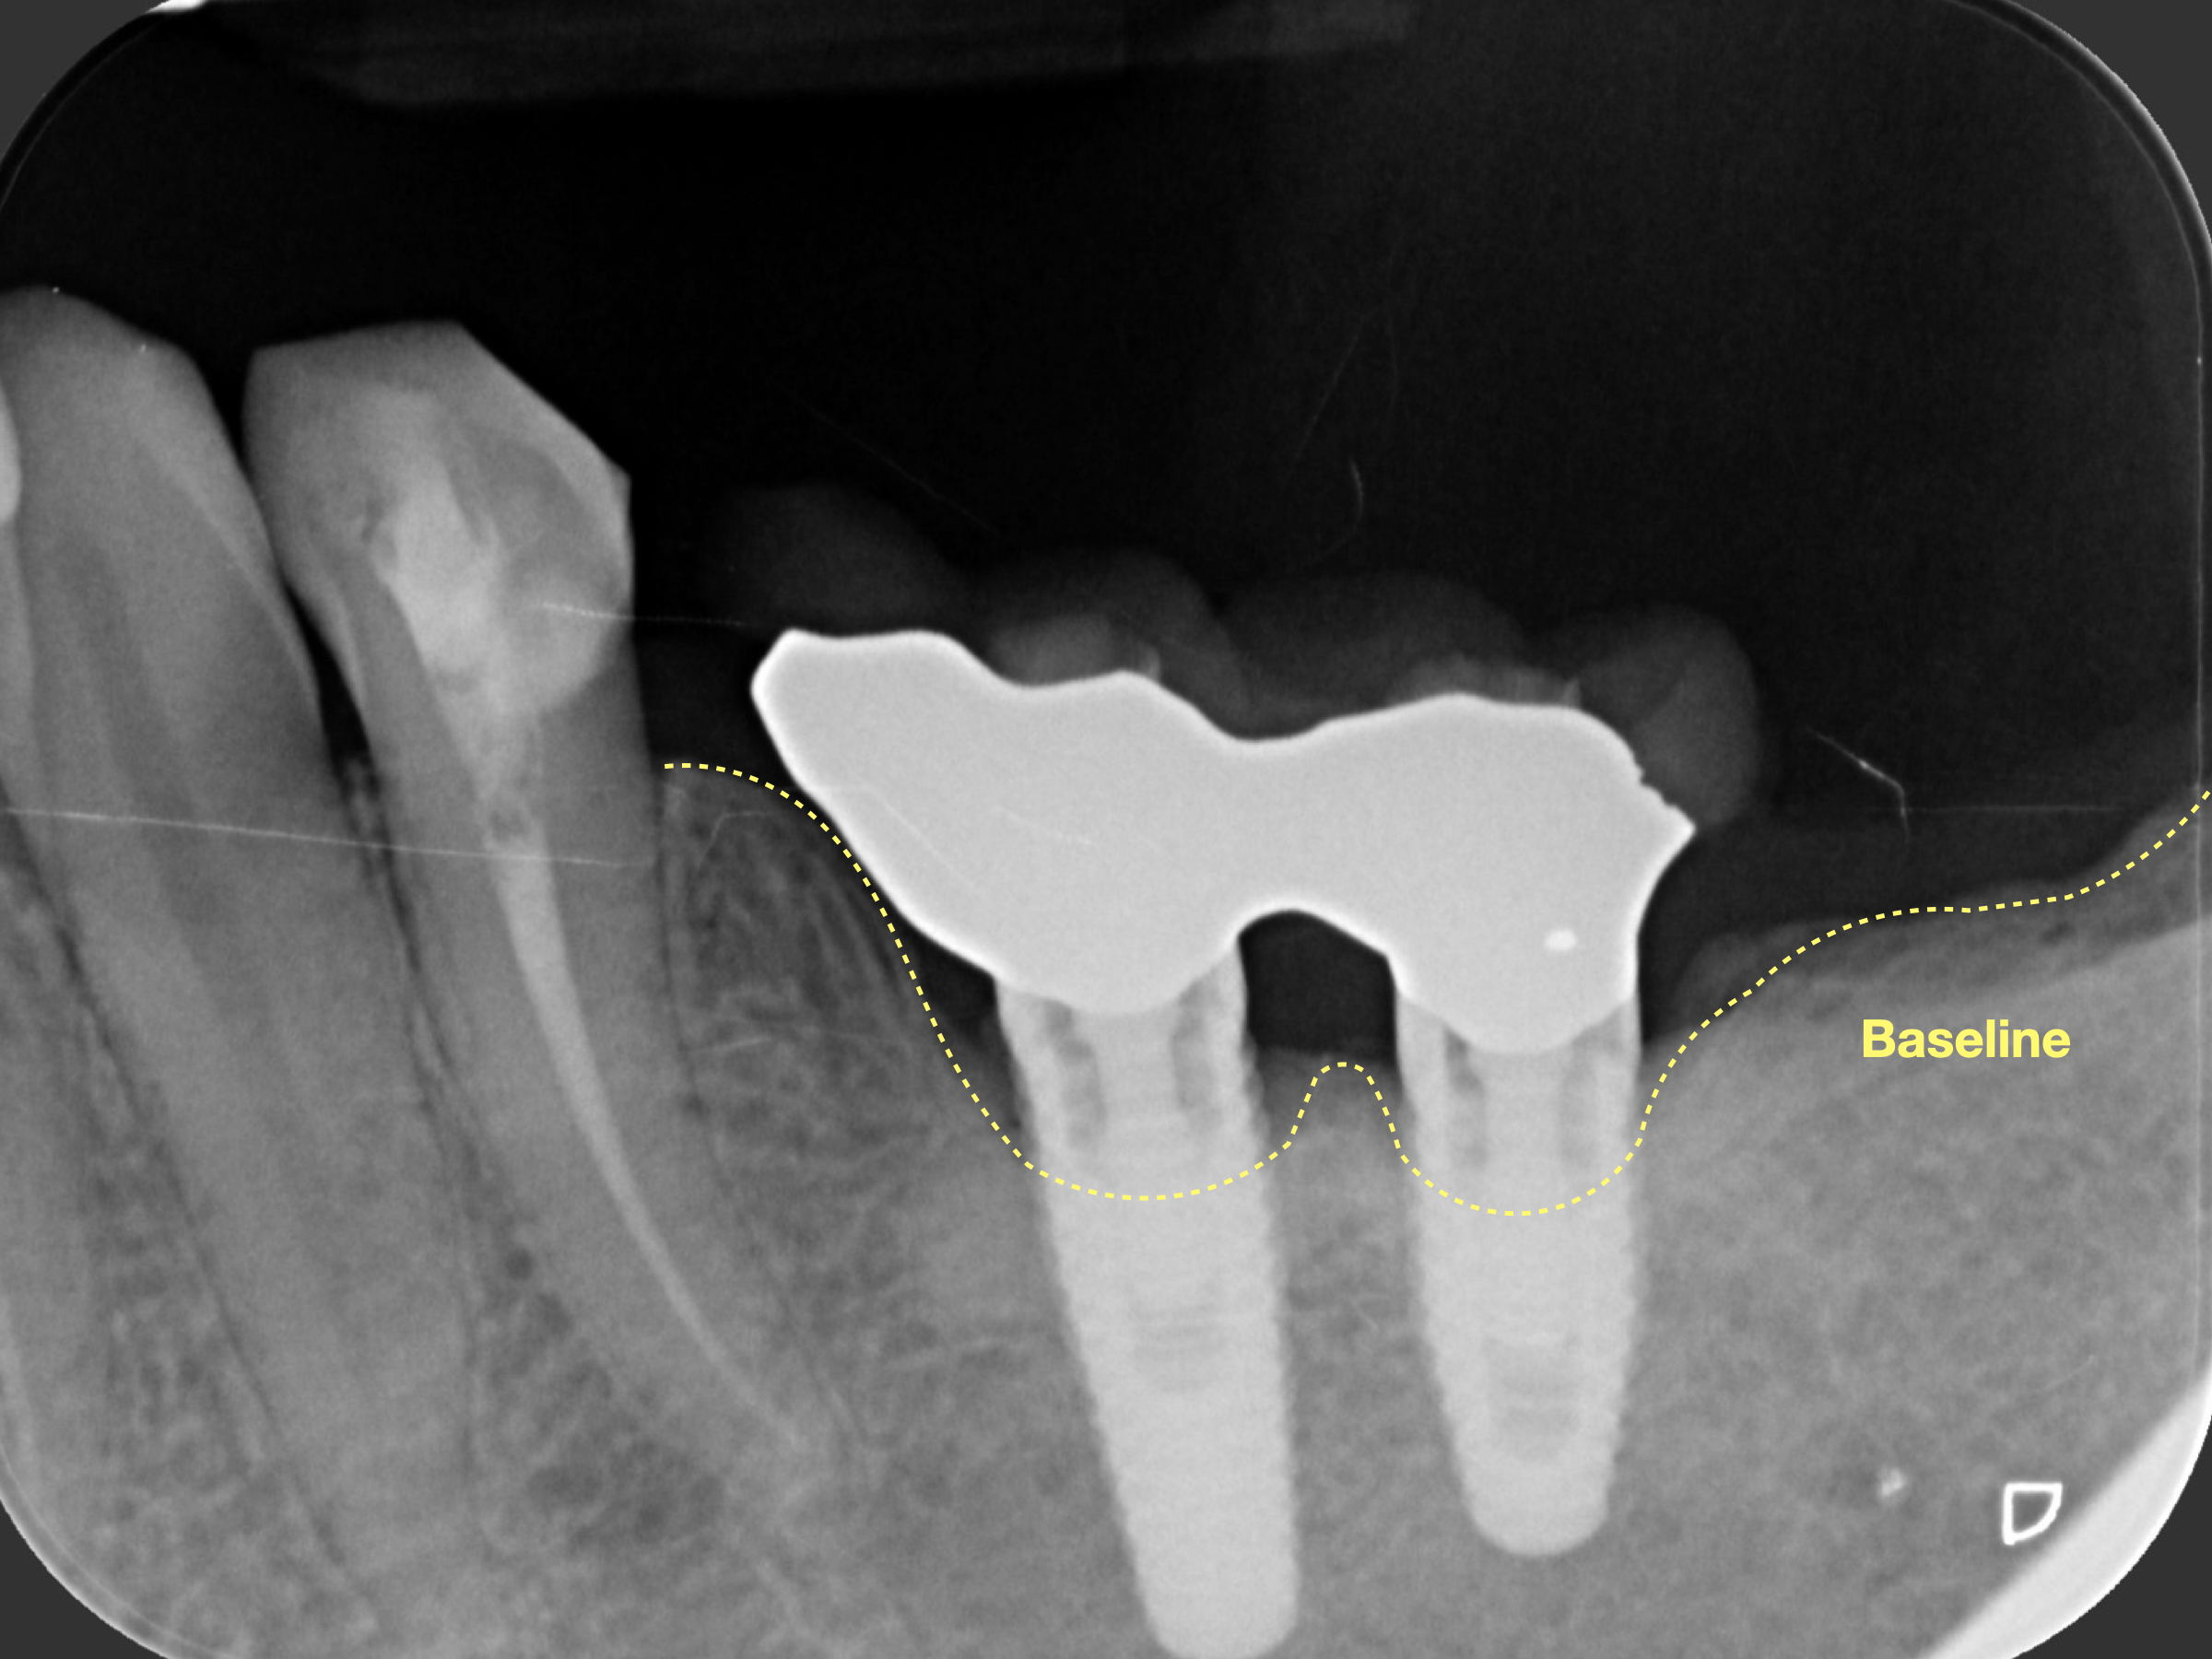

Nel caso clinico che presentiamo, è stata eseguita una GBR (Guided Bone Regeneration), rigenerazione ossea guidata:

📸 Radiografie e foto mostrano chiaramente il recupero del supporto osseo e la stabilità dell’impianto a distanza di mesi.